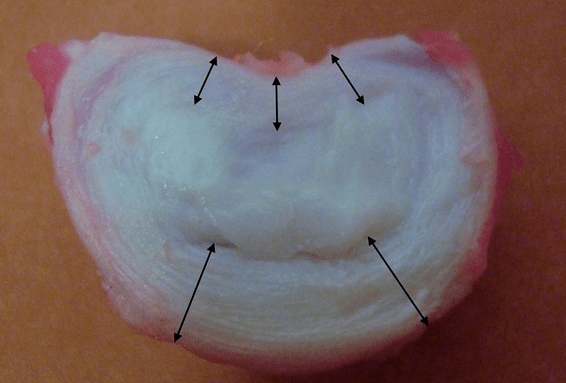

Each intervertebral disc consists of two different parts:

- outer fibrous ring, consisting of dense fibers that cover the disc from the outside along the circumference;

- the internal elastic component is the nucleus pulposus.

The fibers of the annulus fibrosus are very dense and flexible.As the years go by, flexibility is lost, and by the age of 60, the annulus fibrosus becomes rigid.Between the surface of each overlying and underlying vertebrae and the disc itself, there are so-called end plates, i.e. the border zones between the vertebra and the disc.Thanks to these end plates, the vertebrae grow in height, through them the tissues of the nucleus pulposus and the intervertebral disc are diffusely nourished by the diffusion method, since the disc of the intervertebral disc is not supplied with blood and is not innervated.

That is, the thickness of the discs is the greatest in the lumbar region, due to the greatest load.Laboratory studies have shown that a single healthy disc in a young person can withstand a static compressive load of up to 2.5 tons.At the age of 70, this number drops to 110 kg!That is, an "old and dried out disc" copes 22 times worse with transferring the load to the side and maintaining the increased pressure inside the annulus.

Why did this happen?Over time, the fibrous ring gradually wears out.It can no longer extend, it only extends outward, beyond the disc, or it breaks.The core does not transmit and convert the vertical load into radial load.As we age, stress gradually builds up inside the discs and their structure changes.If all these processes are transferred to the entire spinal column on a separate disc, then in the clinic we get a condition called osteochondrosis.Now we can start defining it.